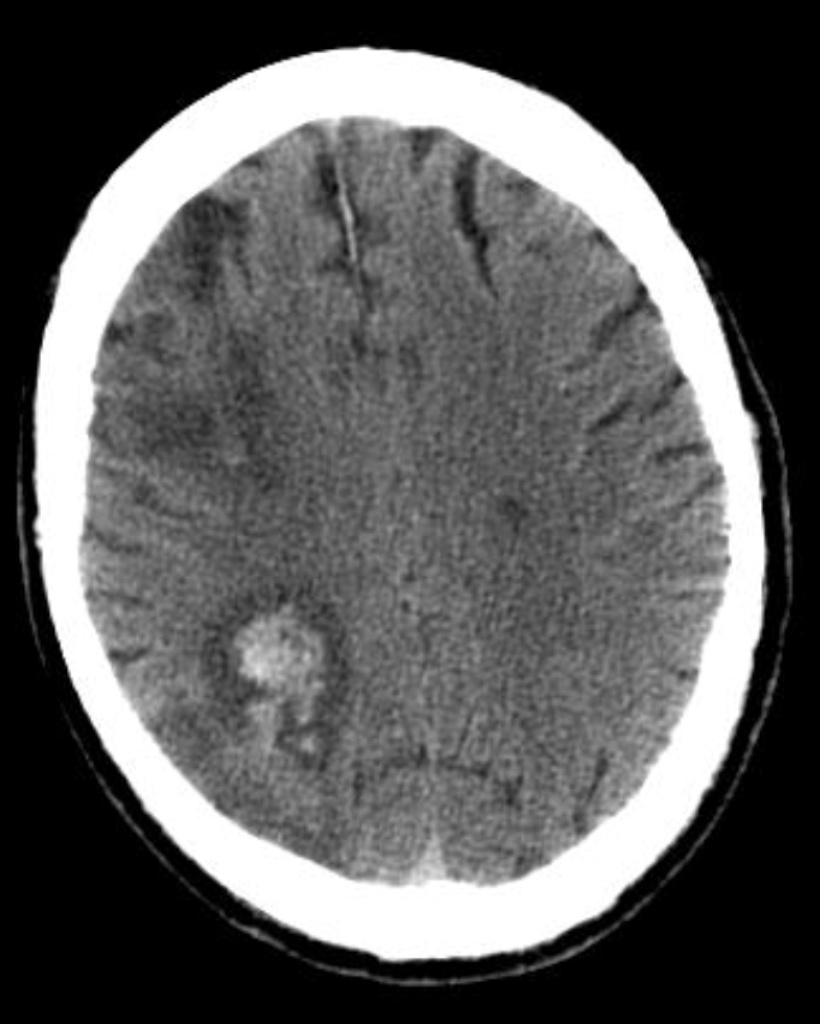

Pathology